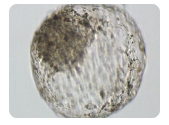

试管婴儿技术是一种辅助生殖技术,适用于无法自然受孕的夫妇。在这个过程中,医生会收集女性卵子和男性精子,并在实验室中将它们结合成胚胎,然后将胚胎移植回女性子宫。这

穿刺取精子和卵子是试管婴儿技术中的一种重要方法。在该方法中,医生会通过一些特殊设备将采集到的卵子和精子进行体外受精。接着,胚胎会在培养皿中发育成为合适大小并且健

试管婴儿属于生殖医学科。试管婴儿技术是指将成熟的卵子与精子结合在体外培养皿中,使其受精形成胚胎,然后将胚胎移植到母亲子宫内发育成为正常的胎儿。试管婴儿技术已经成

试管婴儿是一种辅助生殖技术,即在体外将女方卵子与男方精子结合,培养成胚胎后再移植进女性子宫内进行着床。整个过程需要多次检查和治疗,并不仅仅是一个手术就能完成的。